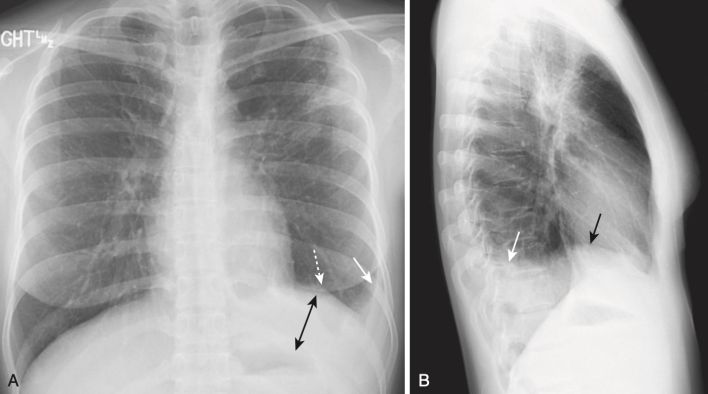

Tràn dịch dưới phổi (Subpulmonic Effusion)

- Hầu hết các tràn dịch màng phổi đầu tiên tập trung ở một vị trí bên dưới phổi giữa màng phổi thành lót bề mặt trên của cơ hoành và màng phổi tạng dưới thùy dưới.

- Nếu tình trạng tràn dịch vẫn hoàn toàn ở dưới phổi, có thể khó phát hiện trên phim chụp X quang thông thường, ngoại trừ những thay đổi đường viền ở nơi dường như là cơ hoành nhưng trên thực tế là ở giao tiếp dịch – phổi bên dưới phổi.

- Các hình thức xuất hiện khác nhau của tràn dịch dưới phổi được tóm tắt trong Bảng 2 (Hình 2 và Hình 3).

- Dưới phổi không có nghĩa là khu trú.

- Hầu hết các tràn dịch dưới phổi di chuyển tự do khi bệnh nhân thay đổi tư thế.

BẢNG 2 NHẬN BIẾT MỘT TRÀN DỊCH DƯỚI PHỔI

.